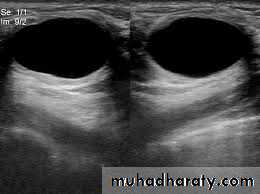

• b-uls both for diagnosis and to guide biopsy

• c-magnetic resonance useful in symptomatic patient with breast implant where US is not diagnostic and also used in to detect local recurrence where US and mammography are un helpful

• These occur in last decade of reproductive life due to a non integrate involution of stromal and epithelium .they are often multiple and may be bilateral and it may mimic breast cancer• Diagnosis by aspiration and or uls after triple

• assessment .